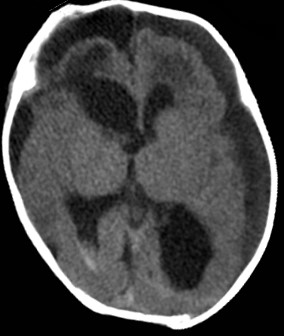

病史:于当地医院检查发现患有脑部疾病,头颅MRI影像检查提示颅内肿瘤合并脑积水。虽经积极的治疗以及护理,病情未见明显好转,孩子头围一天天增大,脑积水症状加重,由当地医院转西安市儿童医院治疗。

复查的头颅MRI检查提示孩子右侧脑室内占位性病变并交通性脑积水、间质性脑水肿,颅内硬膜下出血,增强扫描检查提示肿瘤病变均匀强化,肿瘤血供丰富(如下图)。